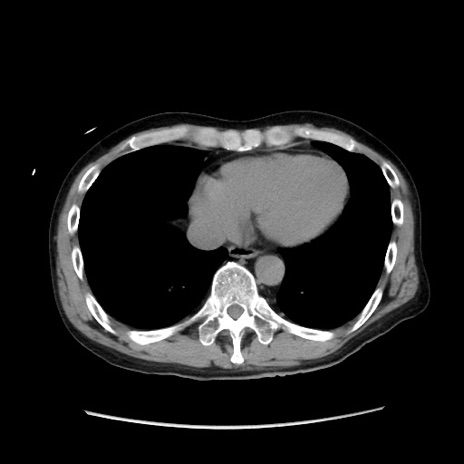

症例37(横断像)

【症例】40歳代 男性

【主訴】腹痛

【現病歴】4時間ほど前に電車に乗車中に臍部上より腹痛出現。徐々に増悪し起立困難となり、救急外来受診。生ものは数日食べていない。今朝お雑煮を食べた。

【身体所見】BT 36.8℃、BP 117/84mmHg、HR 91/min、SpO2 97%、苦悶様、腹部:臍上部広範囲圧痛あり、反跳痛±

【データ】WBC 8100、CRP 0.03